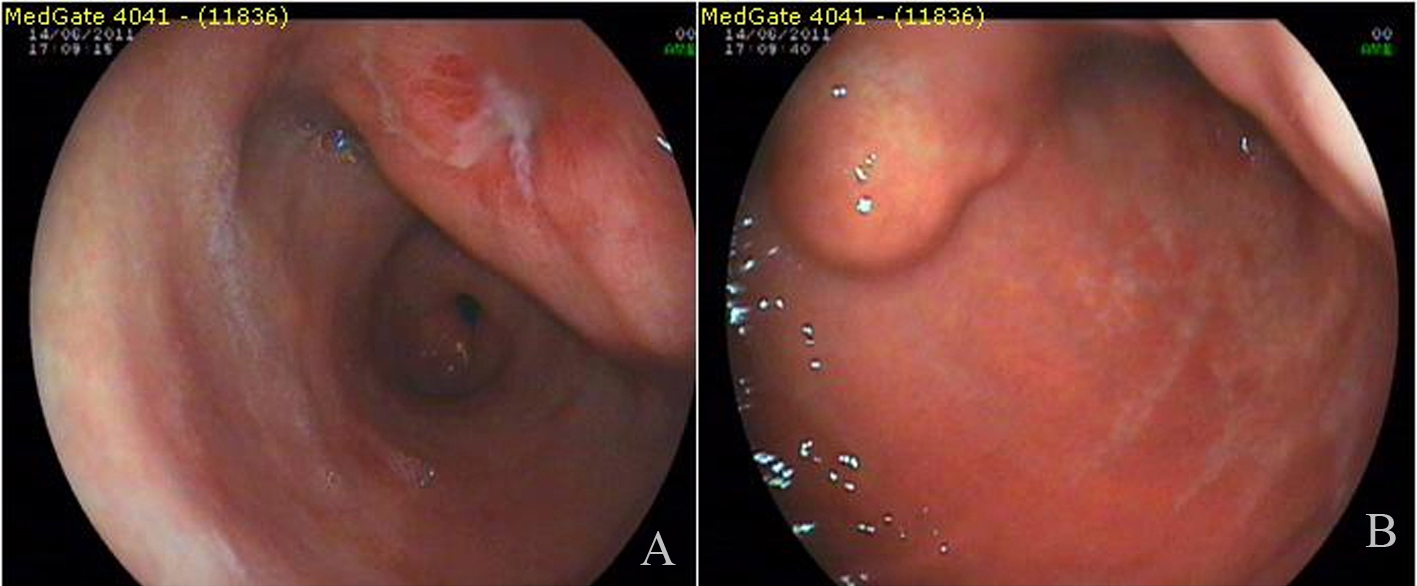

A 3 - 4 cm ulcerated polypoid mass in antrum and polypoid lesion with an impression of submucosal localization over the distal corpus (Fig. 1) were found in endoscopy in a female patient complaining of dyspeptic problems with an age of 54. Endoscopic biopsies revealed chronic inflammation and H.pylori was negative. First, abdominal tomography and then endoscopic ultrasonography were performed. Abdominal tomography showed a polypoid mass in the antrum with a diameter of 6 cm (Fig. 2A). Endoscopic ultrasonography yielded 5 - 6 cm transmural mass with serosal infiltration and heterogenous echogenity. Fine-needle aspiration biopsies were performed two times with a nondiagnostic material. Trucut biopsy was performed after cytologic examination yielding sample rich in lymphoid tissue. Histologic examination was reported as extranodal marginal-zone B-cell lymphoma with CD20 antigen (+) (Fig. 2B). The patient was consulted to Oncology Service for chemotherapy.

![]() Click for large image | Figure 1. Endoscopic appearance of the lesions. |